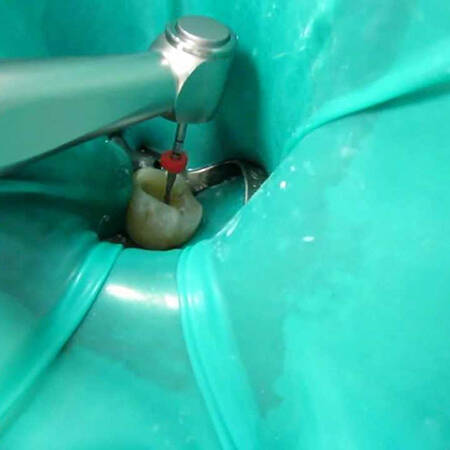

- Limpeza e Desinfecção: O canal radicular é cuidadosamente limpo e desinfetado para remover qualquer resquício de tecido infectado.

- Preenchimento do Canal: Após a limpeza, o canal é preenchido com um material específico que evita novas infecções.

Na Clínica Pontes Odontologia, nossos especialistas em Endodontia utilizam tecnologia avançada e técnicas precisas para realizar tratamentos de canal de forma eficaz e confortável. Garantimos um atendimento de qualidade, com foco no bem-estar do paciente e na preservação da saúde dentária.